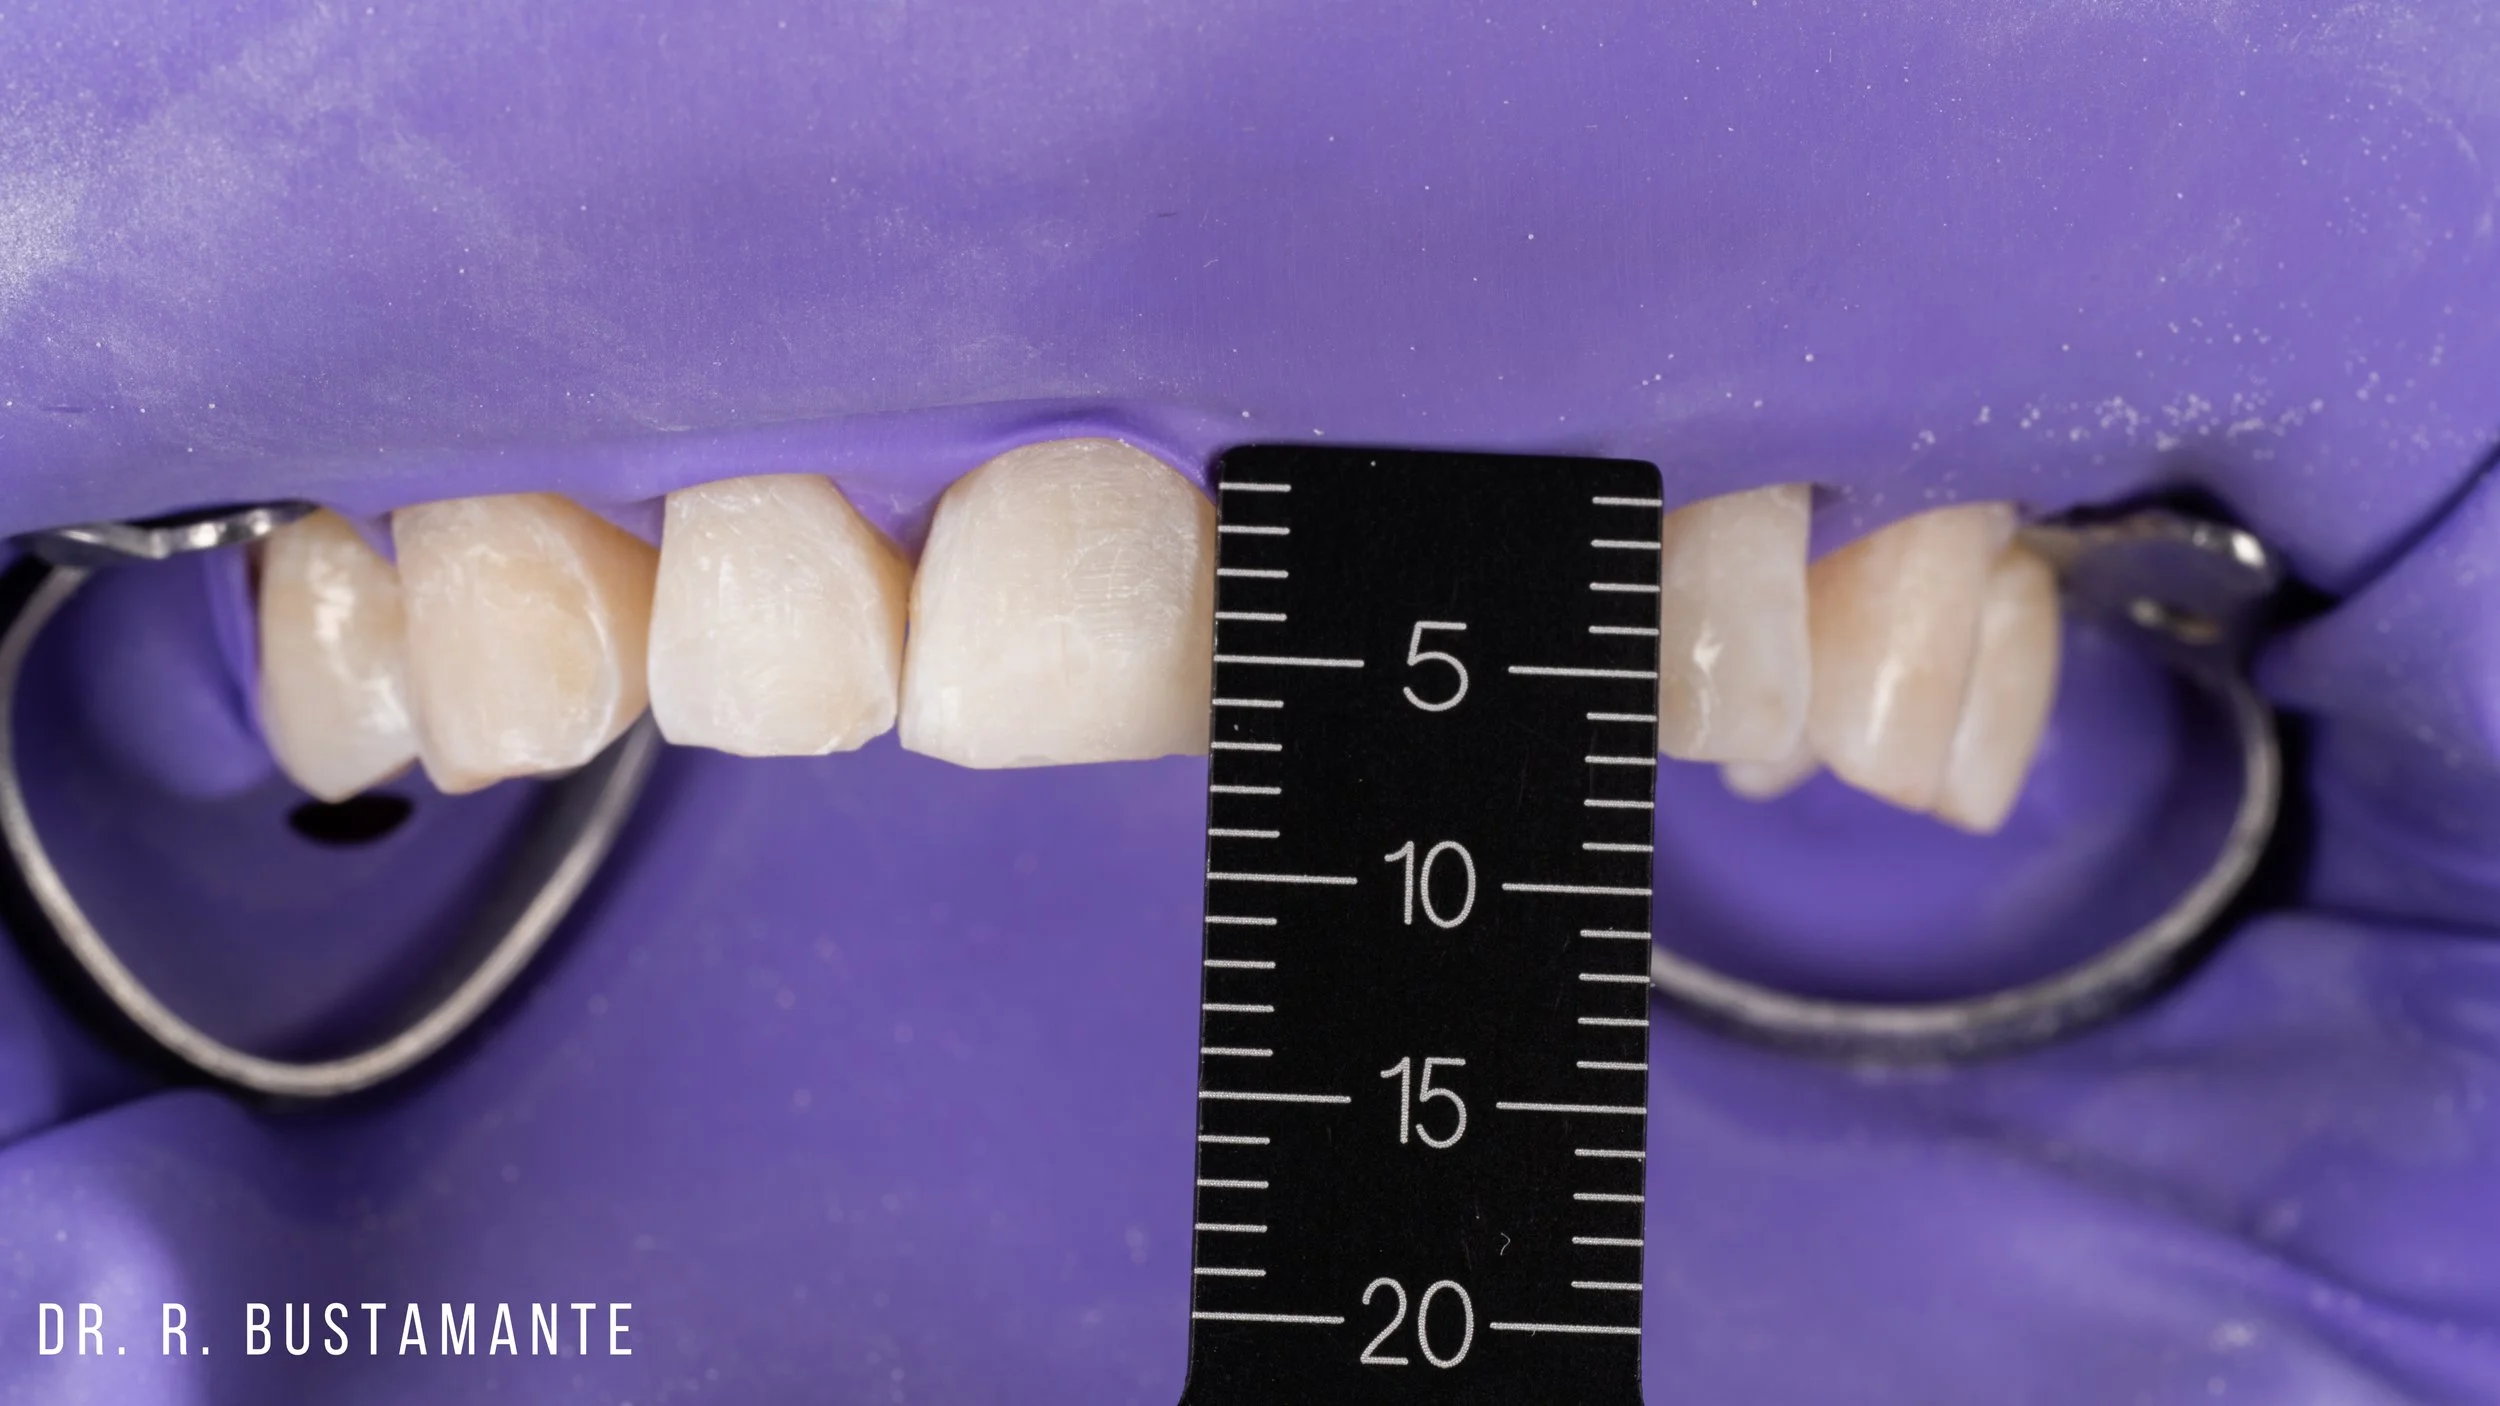

Bioclear offers a transformative solution for enhancing your smile. Whether you’re looking to close small gaps between your teeth (commonly known as black triangles), address uneven, chipped, or broken teeth, or refresh worn, discolored, or decayed teeth, Bioclear delivers natural, stunning results tailored just for you.

The Bioclear Method can rejuvenate the shape, size, and fit of your teeth. Bioclear is a minimally invasive, conservative alternative to rejuvenating worn out, broken, discoloured, and chipped teeth.

Diastema Closure.

Peg Laterals (little teeth).